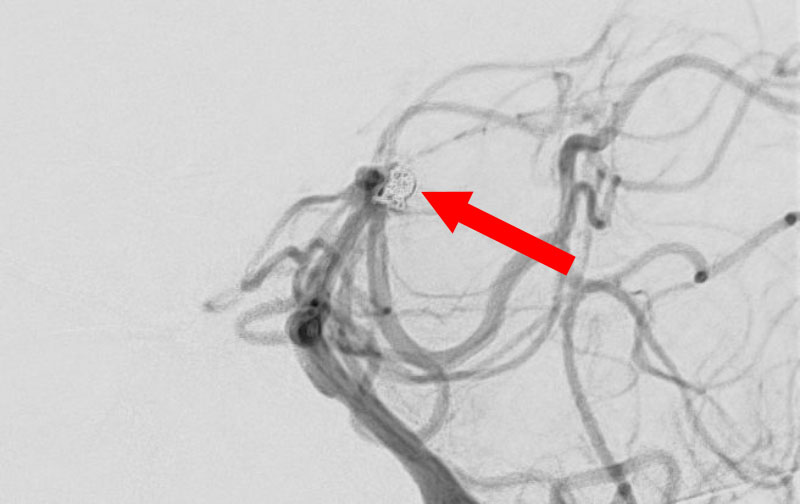

No.1596 手術中